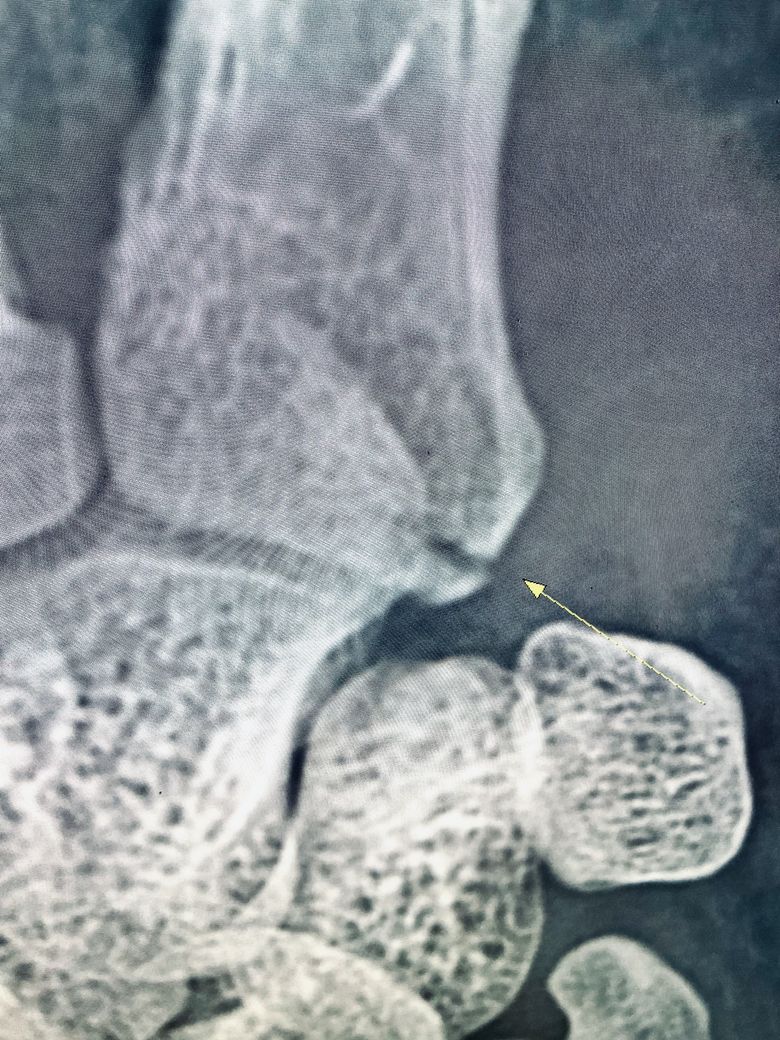

약 두 달 전 (3월 16일) 격투기 운동을 하다가 그라운드상태에서 상대의 등에 오른손이 깔리면서 통증을 느껴 다음 날 정형외과에 방문하여 엑스레이 촬영 결과 오른손 5번 중수골 기저부 골절 진단을 받았습니다.

1주에서 2주사이는 보호대 착용시 통증이 심하여 진통제 복용을 하였으며 3주차부터는 통증이 거의 없어 괜찮은가 하는 생각에 근무중에 보호대를 풀고 손을 쓴다거나 하는 경우가 빈번했습니다 손을 쓰고 난 후 보호대를 착용하면 다시 욱신거리는 통증이 생겼다가 일정시간이 지나면 괜찮아지는것이 반복되었고 마지막으로 병원 엑스레이 촬영시(5월10일-약 7주경과) 뼈가 아직도 붙지 않았다고 하였습니다.